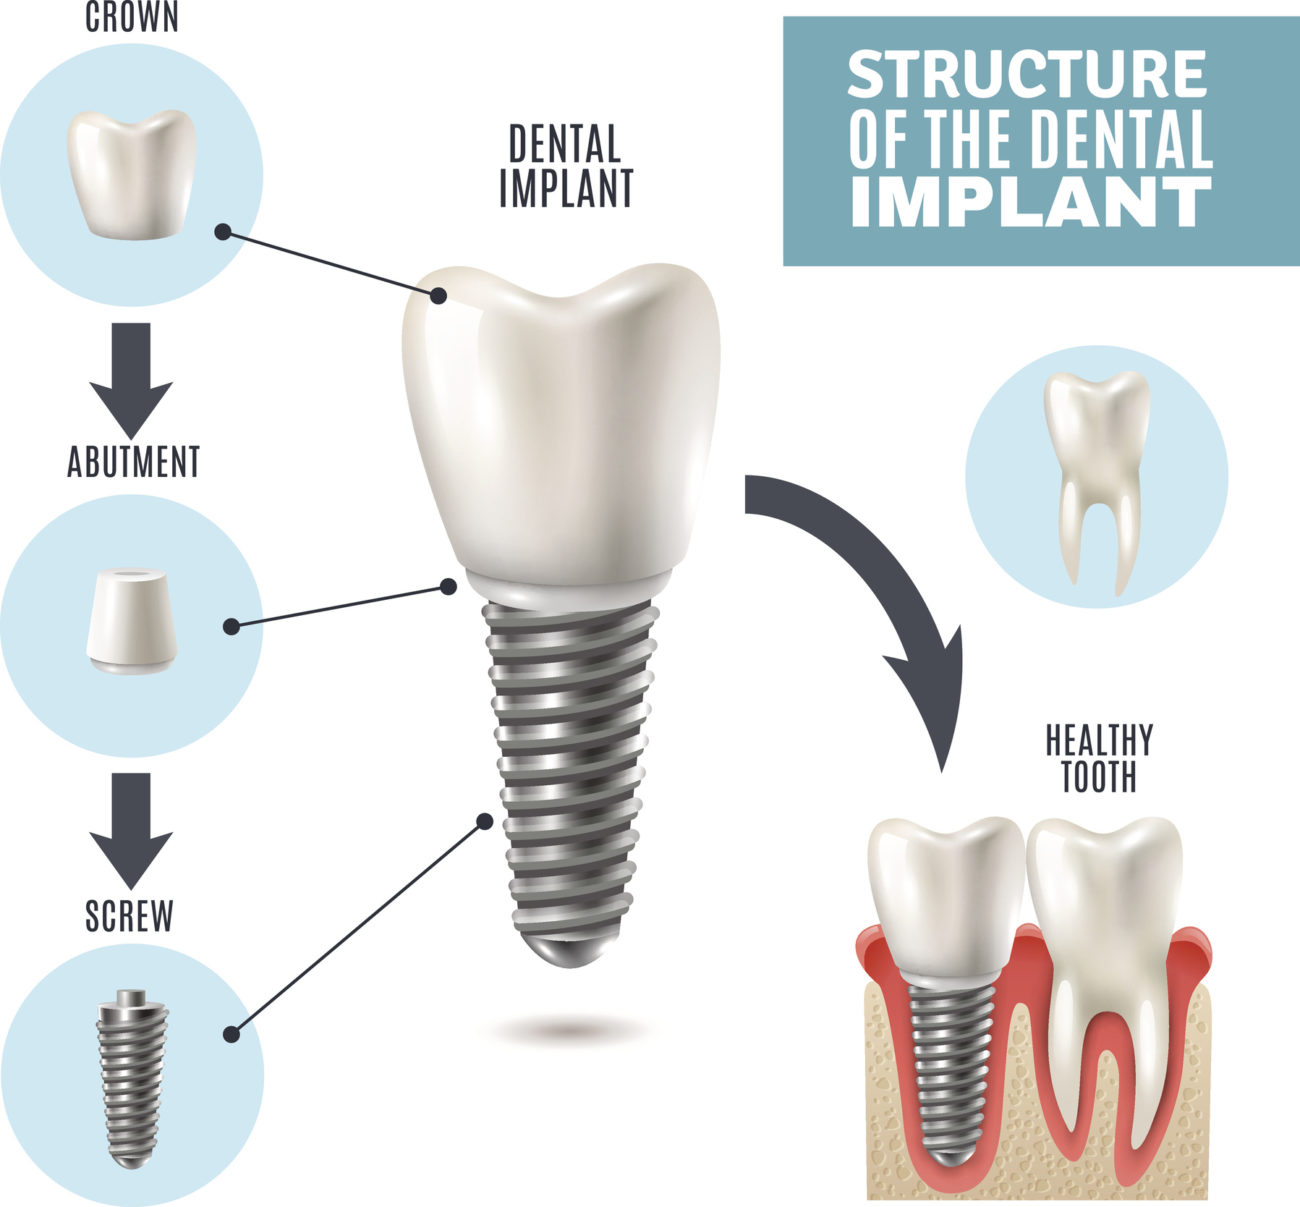

The Anatomy of The Dental Implant | Knoxville TN Dentist

What is a Dental Implant? | DDi

Dental Implant, Single Tooth